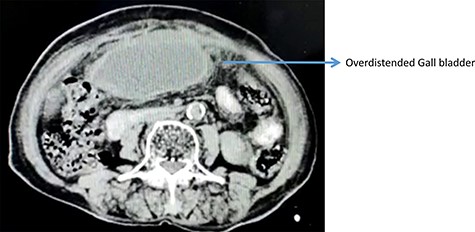

Over distended gall bladder with thickened laminated walls filled with thick internal echoes suggestive of acute cholecystitis without gall stones were the main findings of abdominal ultrasonography (Fig. 1). Color Doppler showed no intramural blood flow in the wall of the GB.

On computerized tomography, there was no additional finding (Fig. 2).

Contrast enhanced computed tomography abdomen showing over distended GB.